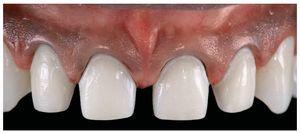

A partir de ésta se prensó el núcleo, el cual fue recubierto con una cerámica vítrea de nano-flúor-apatita (e.max Ceram, Ivoclar Vivadent). Las carillas parciales en los caninos superiores se cocieron sobre un modelo pirorresistente (fig. 31). Se citó al paciente al cabo de tres semanas para la inserción de las restauraciones definitivas.

Figs. 31a y 31b. Las carillas laminadas cerámicas de disilicato de litio (e.max Press/e.max Ceram, Ivoclar Vivadent) sobre el modelo maestro. Las pequeñas carillas parciales en los caninos superiores se cuecen sobre un modelo pirorresistente (e.max Ceram).

Fig. 33. Las cuatro carillas laminadas de los dientes anteriores realizadas en disilicato de litio se colocaron con una pasta de prueba en boca de gran claridad. Éste fue también el color de pasta finalmente seleccionado.